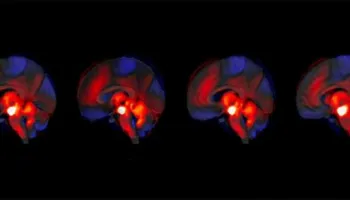

3. Skizofrenia: Roli i papritur i trurit të vogël

Skizofrenia: Roli i papritur i trurit të vogël

Apati, tërheqje sociale dhe humbje motivimi, të ashtuquajturat simptoma “negative” të skizofrenisë, janë ndër më të vështirat për t’u trajtuar dhe më kufizueset për jetën e përditshme. Një ekip nga Universiteti i Gjenevës (UNIGE) ka zbuluar një rol të papritur të trurit të vogël në shfaqjen e këtyre simptomave, përmes ndikimit të tij në sistemin […]